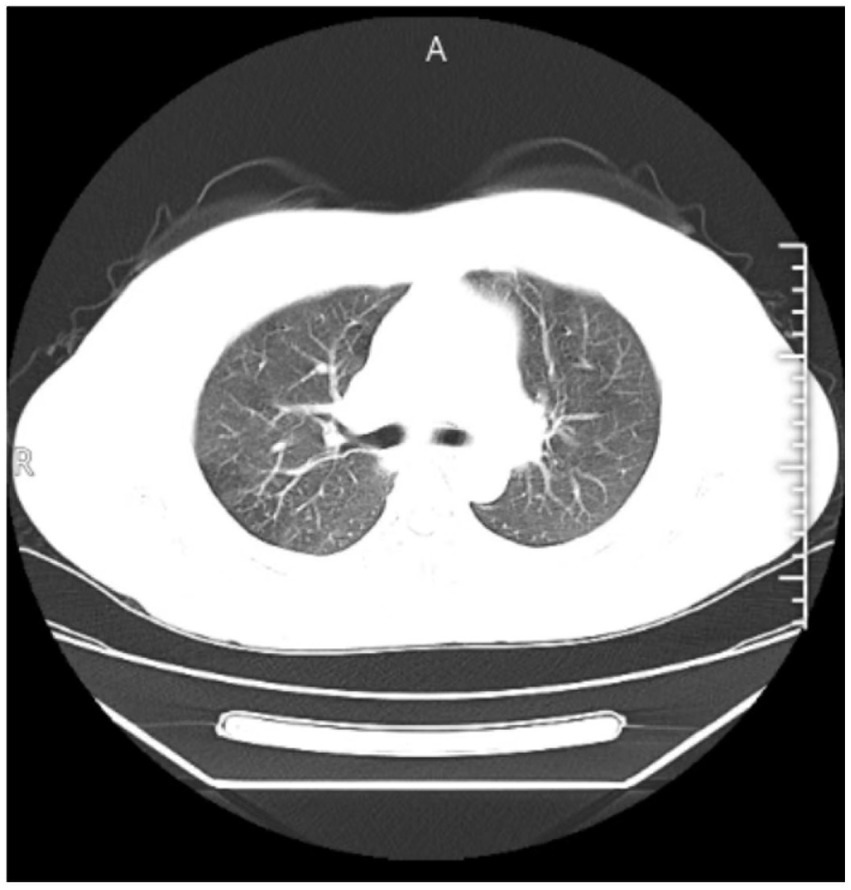

Superficial ultrasonography of the forearm revealed an irregular mass measuring approximately 56.7 mm × 16.4 mm with unclear borders (Figure 1). CT examination of the chest showed no abnormality (Figure 2). The laboratory blood test revealed a hemoglobin level of 131 g/L, leukocytes of 5.13 × 109/L, neutrophil percentage of 70.6%, lymphocyte percentage of 19.4%, eosinophil percentage of 4.68%, and hematocrit of 20 mm/h. Liver and renal function tests were normal.

Figure 2

Chest CT scans showed no significant abnormalities.